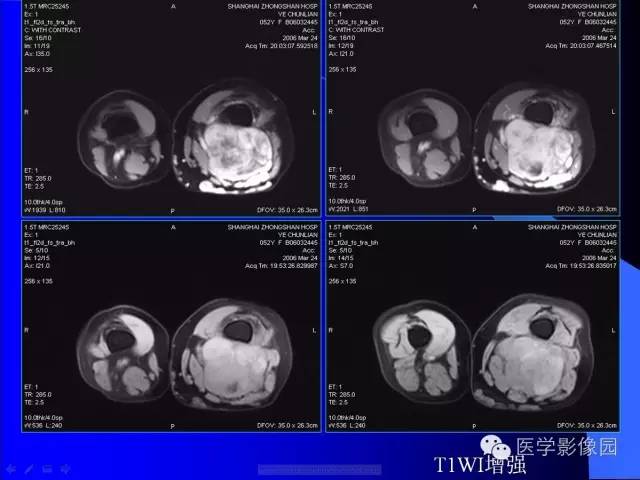

【病例】大腿恶性孤立性纤维瘤1例MR

病史:女,52岁,左大腿包块30年,逐渐长大。

孤立性纤维瘤起源于弥漫分布于人体结缔组织中CD34阳性的树突状间叶细胞。多见于头颈部、上呼吸道、腹腔和周围软组织。发病高峰40~ 60 岁, 女性多见。临床上多数病例表现为局部缓慢生长的无痛性包块。随着包块的增大, 会出现相应部位的压迫症状。孤立性纤维瘤多数病例临床上呈良性经过, 约10% 的非典型性和恶性孤立性纤维瘤局部复发率或远处转移率较高(80% )。